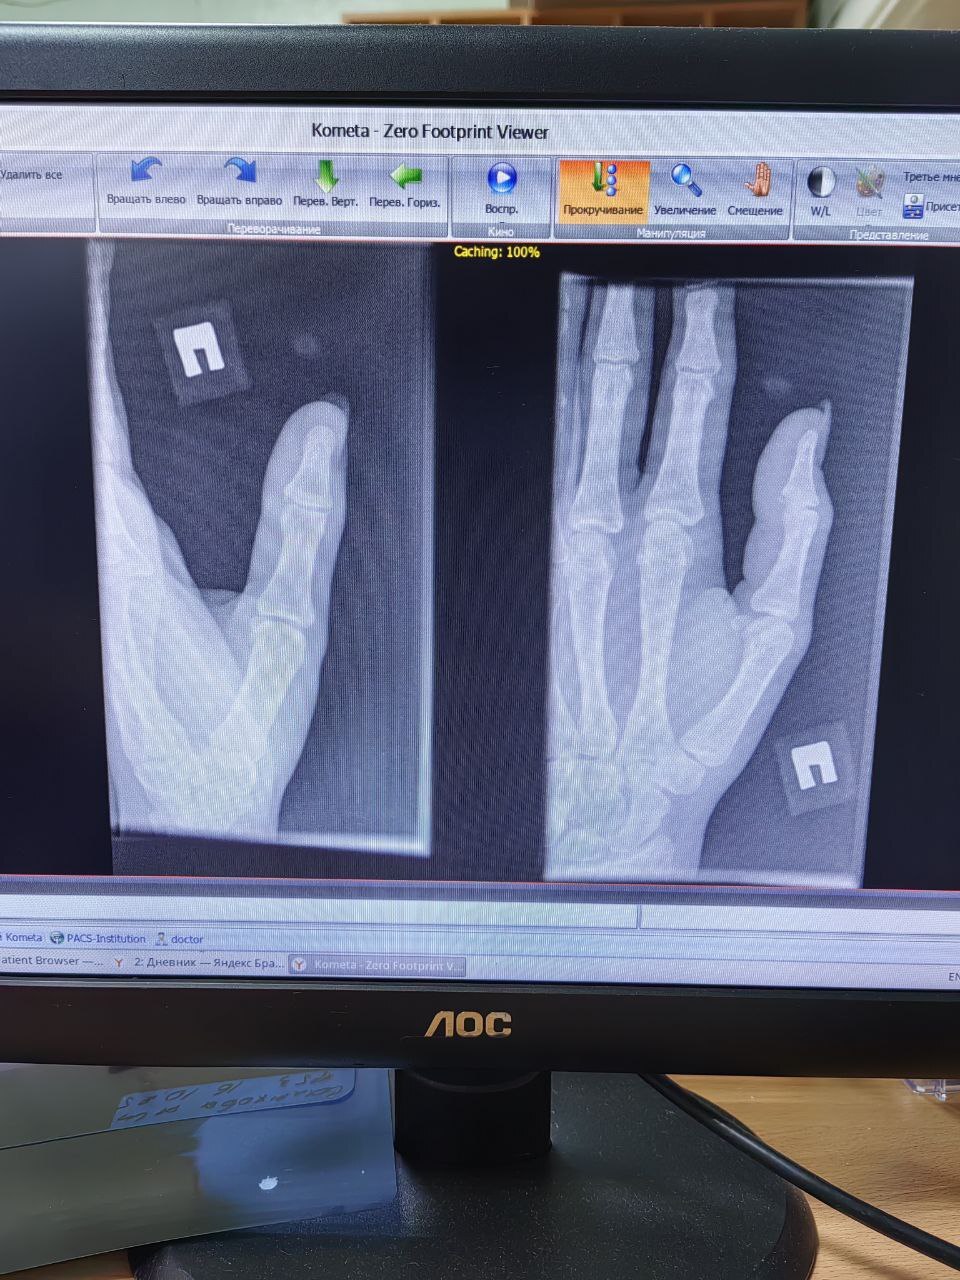

Интереса ради, помогите найти перелом ногтевой фаланги большого пальца.